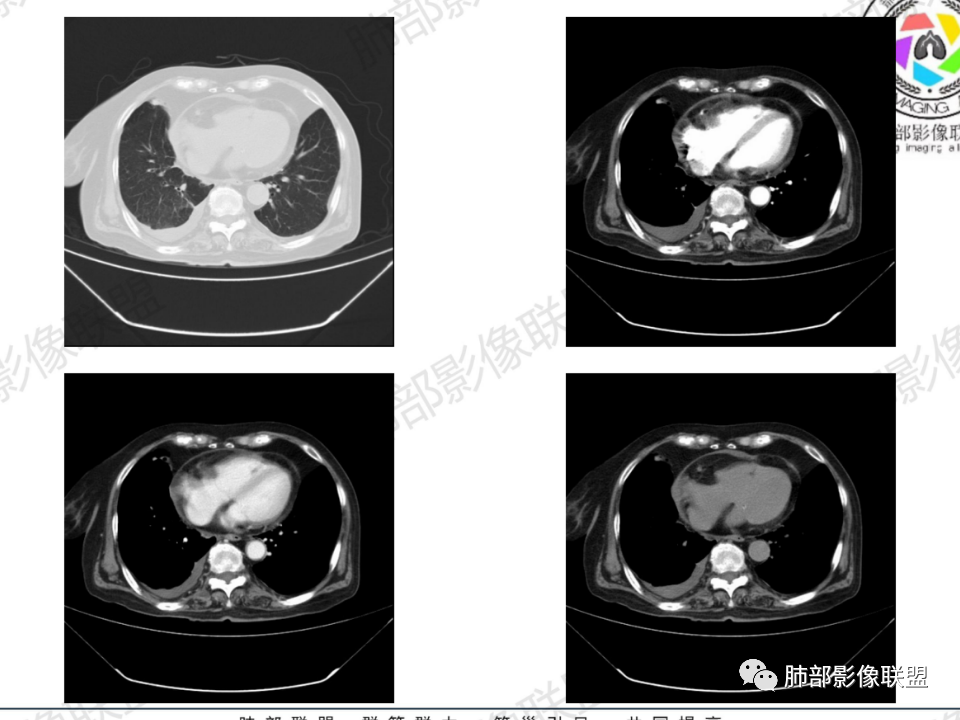

那个人:老年女性,亚急性病程,咳嗽发热。有垂体前叶功能减退,目前激素替代治疗,长期激素,量小,不知道累积量,没有目前激素水平指标。既往有淋巴结结核病史。肿瘤标记物Ca125升高。血沉升高,C反应蛋白轻度异常。影像,右肺上叶靠近肺门团块影,右肺门淋巴结钙化肿大,支气管狭窄,局部增厚,团块影外朝内改变,强化明显,血管破坏不明显,有粘液。和纵隔胸膜分界清楚,周围肺组织有斑片渗出影,右侧胸腔积液,考虑炎性?结核?支气管镜检查除外恶性飞鹰行动:老年患者,影像表现 右肺上叶占位性病变,边界清楚,有分叶征,内见细小钙化,右肺上叶支气管截断,增强病灶不均匀强化,病灶内有条状坏死区(扩张的支气管?),纵膈内未见增大淋巴结,考虑炎性病变,结核可能。一切∮随缘:右肺上叶实性肿块形态不规则,呈三角形,边缘分叶,边界伴有磨玻璃影,近段支气管未见明显显示,可能堵塞,病变平扫密度均匀,增强后可见低密度坏死无强化,周围略强化,右肺下叶散在结节。心包积液,及右侧胸腔积液,临床:有低热,低蛋白血症,肿瘤标记物高,考虑恶性:腺癌,神经内分泌癌(强化偏弱了),淋巴瘤,鉴别:结核红星:老年女性患者右肺上叶,肺门上区 分叶状肿块 ,右肺上叶支气管显示不清,增强扫描肿块,中等程度强化可见小斑片状坏死区,病灶内部可见斑点状钙化灶,病灶周围可见斑片状及小斑点状影,纵膈淋巴结增大,其他区域,胸膜下可见斑点状钙化。考虑肉芽肿性病变,结核的可能性大。老年患者最排除肿瘤性病变腺癌。土娃:右上肺不规则肿块影,边缘分叶,边界磨玻璃影欠清,病灶分叉状,内见点状钙化影及坏死灶,支气管堵塞,病灶增强强化不明显。考虑瘤样结核,鉴别淋巴瘤。张小兵:老年女性,亚急性病程,右肺上叶见不规则肿块,边缘平直凹陷为主,周围GGO边界不清,内见点状钙化及坏死灶,增强持续性渐进强化,右侧少量胸腔积液,双肺门及纵隔肿大淋巴结伴钙化,综合考虑慢性炎症。saf:老年患者,影像表现 右肺上叶占位性病变,边界清楚,有分叶征,增强病灶明显不均匀强化,纵膈内未见增大淋巴结,考虑炎性病变,结核可能。小兜:老年女性,咳嗽喘息一月,发热三天,肿瘤标志物升高,长期激素替代治疗。CT示右肺上叶近肺门不规则实变影,周围伴磨玻璃影,增强持续性渐进强化,内部血管破坏不厉害,内部可见多发条形低密度灶,右侧胸腔可见少量积液,双肺门及纵隔可见钙化淋巴结,考虑为炎性病变,结核可能玫:女,79咳嗽,喘息一月,发热三天入院,右肺上叶不规则形软组织密度肿块影,边界清晰,边缘见分叶及细短毛刺,病灶内见点状钙化影及稍低密度区,病灶边缘呈磨玻璃样改变,增强扫描,病灶呈不均匀性强化,考虑炎性病变,鉴别鳞癌。大雄:老年女性,既往诊断淋巴结结核,提示已治愈,近2年服用激素,诱导结核复燃→发热;纵隔肺门淋巴结肿大钙化,压迫支气管,右肺上中下叶支气管均狭窄→喘息咳嗽;尖段支气管受累闭塞→肺不张、支气管粘液栓;累及胸膜,结核性胸膜炎并胸水→右侧胸痛;实验室,血沉快,CA125高,低蛋白,符合;下一步,支气管镜尖段支气管刷检抗酸染色周太狼:老年女性,亚急性病程,肿瘤标志物升高。CT示右肺上叶尖段不规则肿块影,有分叶、收缩,周围伴磨玻璃影,增强渐进强化,内部可见多发条形低密度灶,右侧胸腔及心包少量积液,纵隔内淋巴结稍增大。倾向于恶性病变,肺癌伴阻塞性炎变可能。丽:老年女性,右肺上叶不规则软组织肿块,边缘清晰,内密度不均,可见点状钙化及粘液栓,周围可见片状高密度影,增强后均匀强化,内多发低密度,纵膈多发钙化淋巴结,考虑结核可能大,建议结合支气管镜检查除外肿瘤宇宙:右胸廓缩小,右肺上叶团块影及不张,平直边,周围磨玻璃影,纤细胸膜牵拉,上叶尖段支气管堵塞,明显延迟强化,可见支气管粘液栓,两肺门钙化淋巴结,右侧胸水,考性炎性肉芽肿,鉴别腺癌王秀仙:右肺上叶肺门区肿块,上叶支气管开口阻塞,形态不规则,密度不均,内可见支气管粘液栓及多发小灶性坏死,周围磨玻璃影边缘模糊,渐进强化,右侧胸腔积液、胸膜钙化,考虑炎性肉芽肿性病变,慢性炎症。鉴别鳞癌,结核。刘丹:老年女性,右肺上叶肿块伴钙化,右肺上叶支气管截断,增强后均匀强化,周边可见点片状模糊影,右侧胸腔积液,右肺门淋巴结增大,考虑占位并阻塞性炎症,肿瘤?结核?建议纤支镜检查。小飞:右肺上叶纵隔旁软组织肿块,边缘深分叶、长毛刺及毛刷样短毛刺,边缘磨玻璃影,磨玻璃边界模糊,支气管截断,平扫密度不均,可见点状钙化,增强不均匀明显强化,心影增大,心包积液,右侧胸腔积液,考虑恶性肿瘤,腺癌?秦化君:右肺上叶不规则分叶软组织密度肿块,边缘清晰,胸膜牵拉,周围花花草草,上叶尖段支气管阻塞,内可见点状钙化,增强后密度不均可见支气管粘液栓及坏死区,内见血管分枝。中间段及中叶,下叶支气管狭窄,壁见钙化。右肺门淋巴结肿大,右侧胸腔积液,心包粘连肥厚。考虑1右上肺恶性病变,鳞癌?2右肺多叶段支气管狭窄,考虑支气管内膜结核?3胸腔积液及肺门淋巴结肿大,转移?风儿:老年女性,右肺上叶肿块,形态不规则,外围大内带小,边缘分叶膨隆平直及毛糙,密度不均,内见支气管粘液栓及多发小灶性坏死,坏死边缘清晰 ,渐进强化,上叶尖段支气管阻塞,叶支气管壁有局限性增厚,邻近胸膜腔微积液;纵隔及双肺门淋巴结肿大,部分钙化,右侧胸腔积液、心包积液、胸膜钙化,考虑炎性,肉芽肿性结核可能性大。鉴别鳞癌,女性及血供均不支持;腺癌,坏死边界太清晰。流心明智:老年女性,79岁,咳嗽、气短1月,发热3天。胸CT:右肺上叶见不规则肿块,边缘有膨隆、有平直凹陷,周围GGO边界不清,病灶内见点状钙化、粘液栓,尖段支气管未见,增强持续性渐进强化,右侧少量胸腔积液,双肺门及纵隔肿大淋巴结伴钙化,肺动脉增粗。考虑:右上叶尖段堵塞并慢性炎症,支气管TB并结石?鉴别Ca

胸腔积液并胸膜钙化,符合结核;

结核是肯定有。现在最大问题是尖段

临床信息:老年女性,亚急性病程,咳嗽发热。有激素使用史。既往有淋巴结结核病史。肿瘤标记物Ca125升高。血沉升高,C反应蛋白轻度异常。 影像所见:右侧胸廓相对狭小,右肺上叶不规则团块影贴附纵隔旁,轻度分叶,整体密度较均匀,偶见钙点。

相应上叶尖端及前段支气管开口未能追踪(阻塞),开口处见钙化。病灶渐进性强化,并衬托出较完整尖段及前段含液支气管影。支气管开口区域未见异常高密度强化(如类癌等)及相对乏血供区(如鳞癌)。病灶区未见液化坏死。右上纵隔及胸廓入口区未见病灶胸膜外突破(栽赃)。

右肺上叶后段等区域散在片状影,边界不清(提示渗出性病灶)。

纵隔及双肺门见钙化淋巴结。心包积液,右侧胸腔积液(提示存在活动新病灶)。双侧胸膜下见多发斑点状钙化,胸廓变形(提示存在结核基础病变可能)。 诊断意见:综上,右肺上叶块状影更符合继发性肺结核。 最后小结:既往诊断淋巴结结核,提示已治愈。近2年服用激素,可疑诱导结核复燃,也可引起发热。纵隔肺门淋巴结肿大钙化,压迫支气管,右肺上中下叶支气管均狭窄,所以引起喘息咳嗽。尖段支气管受累闭塞,导致肺不张、支气管粘液栓,出现条状无强化区。病变累及胸膜,导致结核性胸膜炎并胸水,引起右侧胸痛。实验室检查血沉快,CA125高,低蛋白,均符合结核。下一步,建议支气管镜尖段支气管刷检并抗酸染色。(本段摘自於雄老师精彩发言)